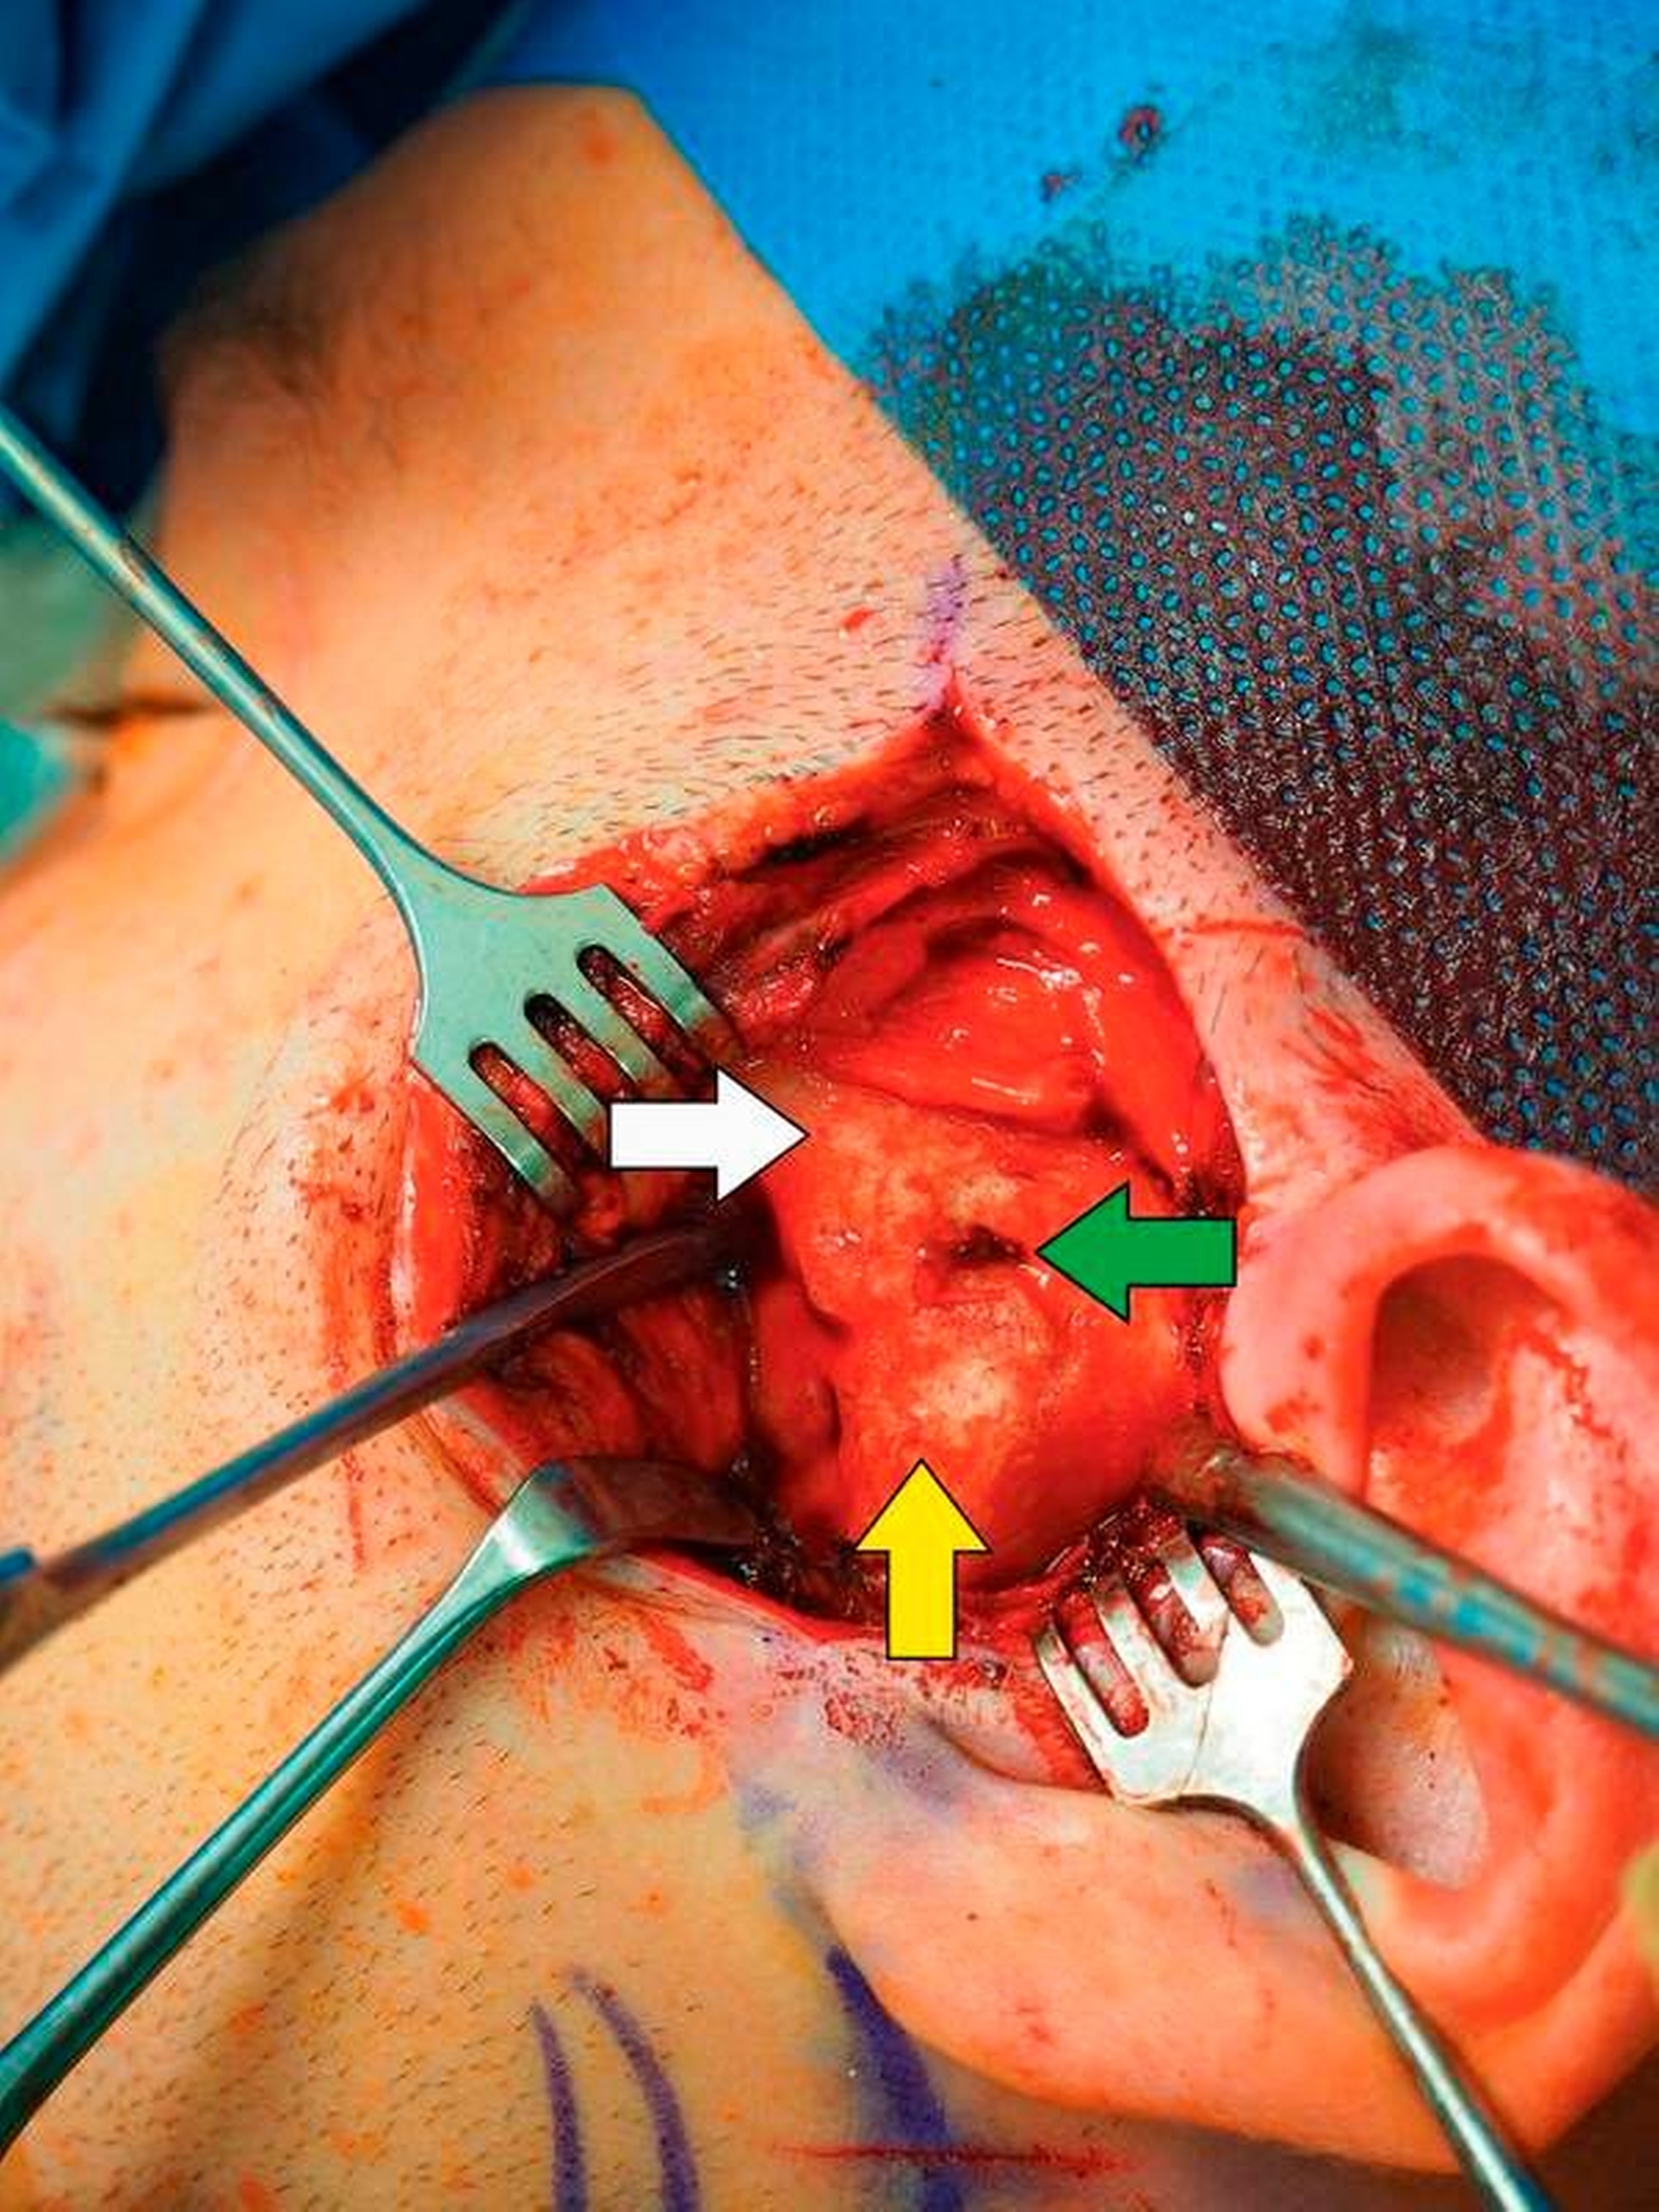

Nach Akzeptanz des Behandlungsplans wurden die TEPs (Totalendoprothesen) beidseits über jeweils einen präaurikulären und einen retromandibulären Zugang implantiert. Diese Prothesen wurden mit Schrauben – mit exakt am CT-Datensatz definierten Schraubenlängen – fixiert. Bei der Planung der Schraubenpositionierung wurde der Verlauf des N. alveolaris inferior berücksichtigt und der Nerv geschont.

Vor der definitiven Fixierung der Prothesen wurden Dummys als Test eingesetzt, um eine optimale Positionierung der passgenauen finalen Prothesen zu erreichen (Abbildung 2 bis 9). Abbildung 10a und 10b zeigen die postoperative Röntgenkontrolle.